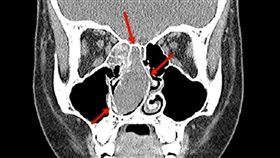

高中生反覆頭痛 竟是鼻子出了問題

16歲蔡姓高中生一年前開始反覆頭痛,初期診斷為偏頭痛...